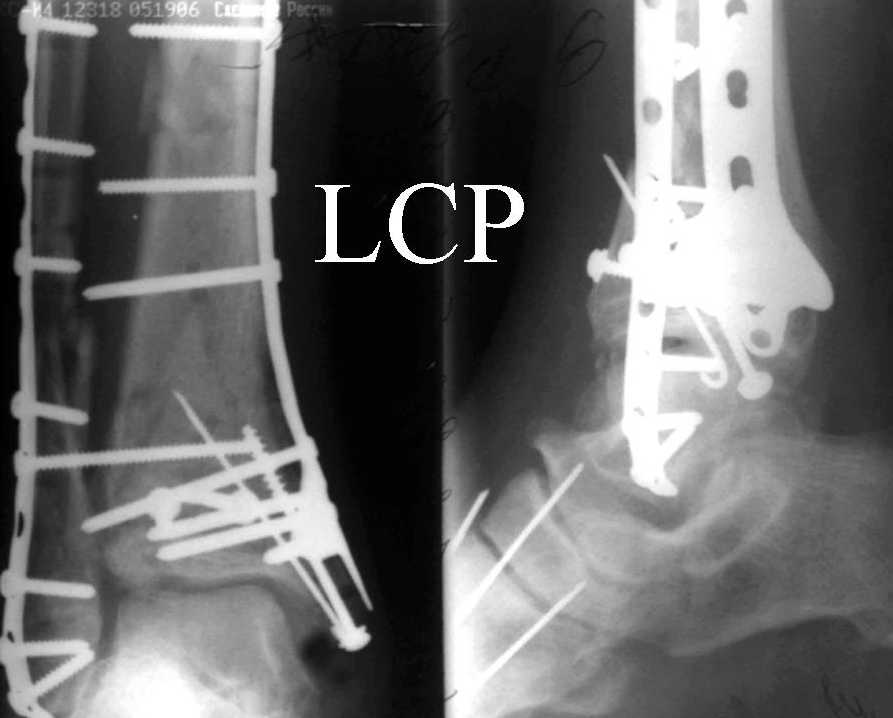

Это типичный перелом пилона, который надп лечить только открыто.Извини те что опоздал к обсуждению, но даже если вы уже оперировали больного по Илизарову это даже лучше.Посылаю картинки.